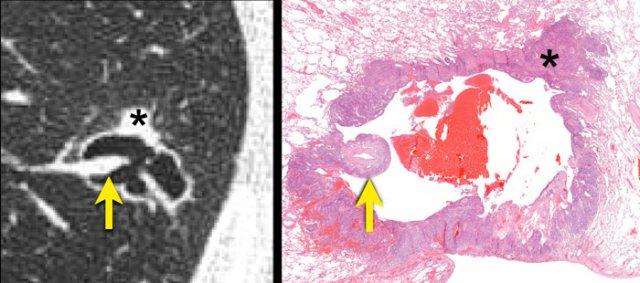

Tương quan hình ảnh học – mô bệnh học của ung thư biểu mô tế bào vảy.

Một khoang khí dạng nang được lót bởi các tế bào khối u (dấu hoa thị) nhiều khả năng đại diện cho một đường thở xa bị giãn rộng.

Cơ chế thông khí van một chiều do hẹp đường thở ở phía gần hơn bởi các tế bào ác tính và/hoặc xơ hóa được cho là nguyên nhân.

Một động mạch phổi kề cận với các tế bào ác tính bao quanh nhô vào trong lòng mạch (mũi tên).